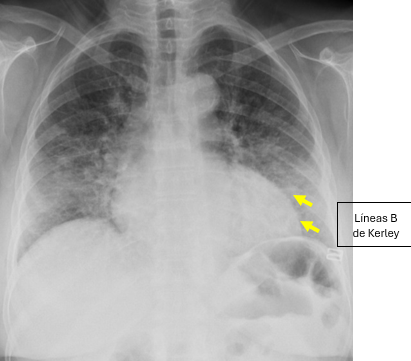

Cuando aparecen alteraciones radiológicas, el patrón más característico es un patrón intersticial reticular o reticulonodular, resultado de la infiltración tumoral de los vasos linfáticos pulmonares y del tejido intersticial. Este patrón se manifiesta como un aumento de la trama pulmonar con líneas finas que configuran una red irregular en ambos campos pulmonares. Uno de los signos radiológicos clásicos es el engrosamiento de los septos interlobulillares, que en radiografía puede manifestarse como líneas de Kerley, especialmente las líneas B de Kerley, visibles en las bases pulmonares como líneas cortas horizontales que contactan con la pleura. La distribución de las alteraciones suele ser bilateral y relativamente simétrica, con cierto predominio en los lóbulos inferiores.

La evaluación radiográfica se ve parcialmente limitada en este caso por el aumento de densidad en la pared torácica anterior, relacionado con la presencia de prótesis mamarias bilaterales secundarias a mastectomía previa. Las prótesis generan una mayor atenuación de los rayos X en la región anterior del tórax, lo que puede producir cierta superposición y disminuir la nitidez de la visualización del parénquima pulmonar adyacente, especialmente en las zonas inferiores y anteriores de los campos pulmonares.